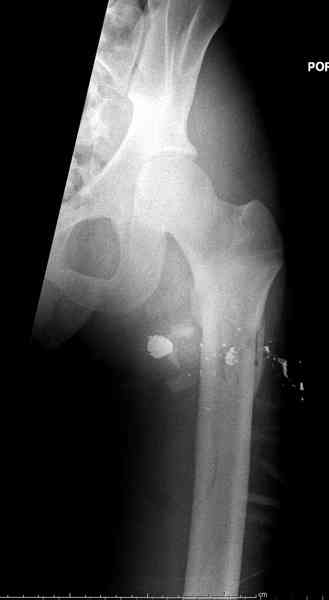

В приложении пример огнестрельного ранения бедра, оперированного на 2 сутки после ранения.

Штифтование было выполнено только на вторые сутки по причине задержки перевода из другого госпиталя, АБ профилактика была начата в другом учреждении, с момента госпитализации пациента к ним. Входное пулевое отверстие и зона введения штифта зажили первичным натяжением.

В конце 90-ых попалось несколько статей по nail exchange procedures in treatment of posttraumatic osteitis и решился попробовать на огнестрельных переломах, которые до этого лечил по полной схеме:расширенный дебрайдмент+ внешняя фиксации+промывные системы с антибиотиками и без антибиотиков в промывной среде. Всё заканчивалось длительной госпитализацией, плохими функциональными результатами( страдала функция колена), необходимостью повторной хирургией - отсроченная внутренняя фиксация переломов, длительной реабилитацией. На гвоздях процесс пошел лучше: остеомиэлитов не было и больные мобилизовывались быстрее.

Единственно что наблюдал - замедленная консолидация, судя по серийным Рг граммам. В приведенном случае прии вялом мозолееобразовании сделал ошибку, решившись динамизировать гвоздь - перелом сросся со значительным укорочением бедра - повторная хирургия по удлинению бедра и проксимальным запиранием, больной мобилизован и вполне доволен(кстати заметить больной с ВИЧ инфекцией - изначально скомпрометированный иммунитет и несмотря на это, всё прошло без костной и мягкотканной инфекции.